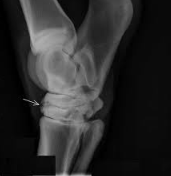

悪性骨腫瘍のなかで、家畜に多発するものは骨肉腫(osteosarcoma)です。

骨肉腫は壮老齢の犬、とくに大型犬の四肢の長骨・肋骨に発しやすく、通常悪性度が高く、しばしば肺に転移し、動物は悪液質に陥って斃死するものが多い。